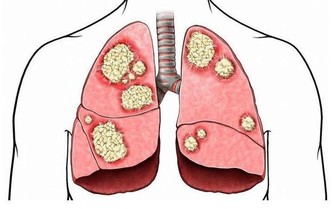

大家可能都知道肝臟是重要的解毒器官,但你們可能不知道,

如果肝臟受到損傷,身體各處肯定得不到血的滋養,

最突出的信號就是皮膚出現粗糙、變黃和長斑,指甲也會變得凹凸不平。